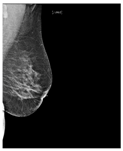

| ACR Class | Feature | Tissues Proportion | Example |

|---|---|---|---|

| A | Fatty | Less than 25% dense tissue | ![]() |

| B | Fibro-glandular | 25–50% dense tissue | ![]() |

| C | Heterogeneously dense | 50–75% dense tissue | ![]() |

| D | Extremely dense | More than 75% dense tissue | ![]() |